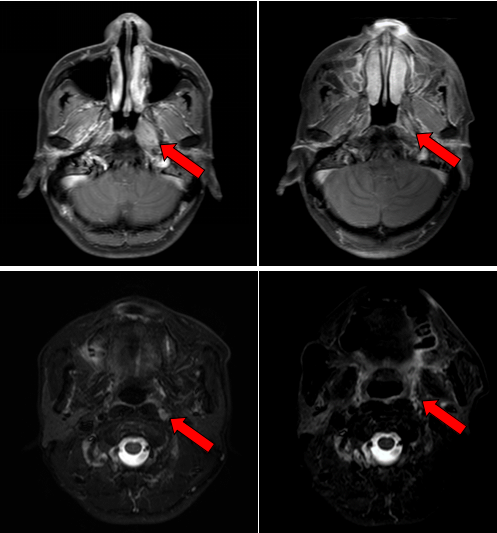

治疗前后鼻咽部病灶、咽后淋巴结病灶对比( 左:治疗前,右:治疗后)